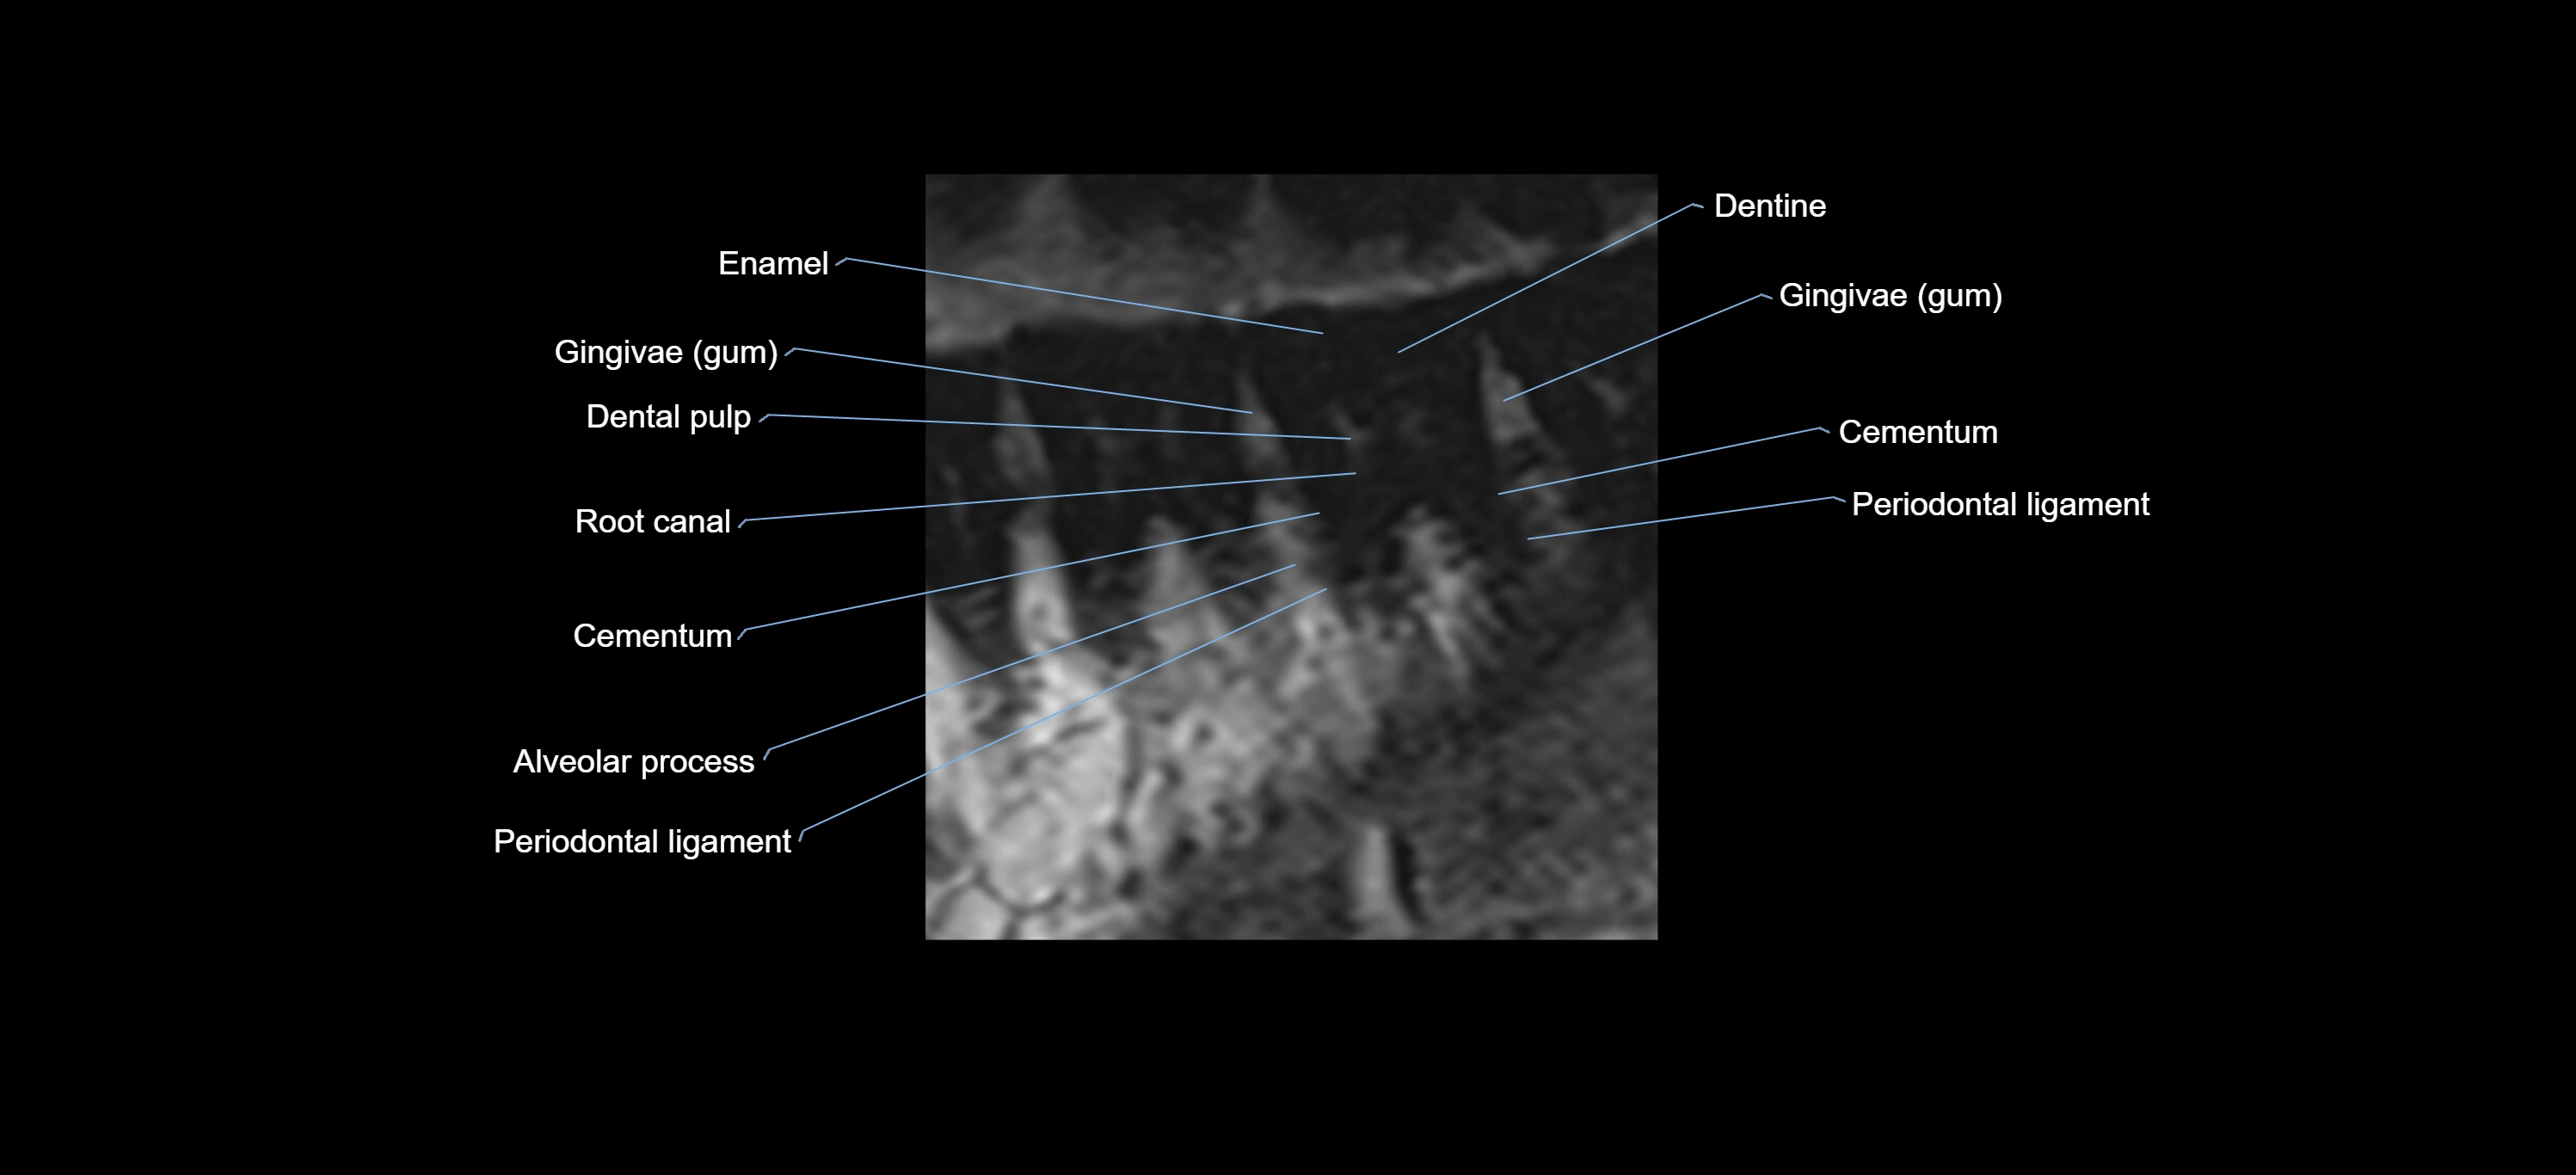

- Gum (gingiva)

- Root canal of upper molar tooth

- Root canal of upper premolar tooth